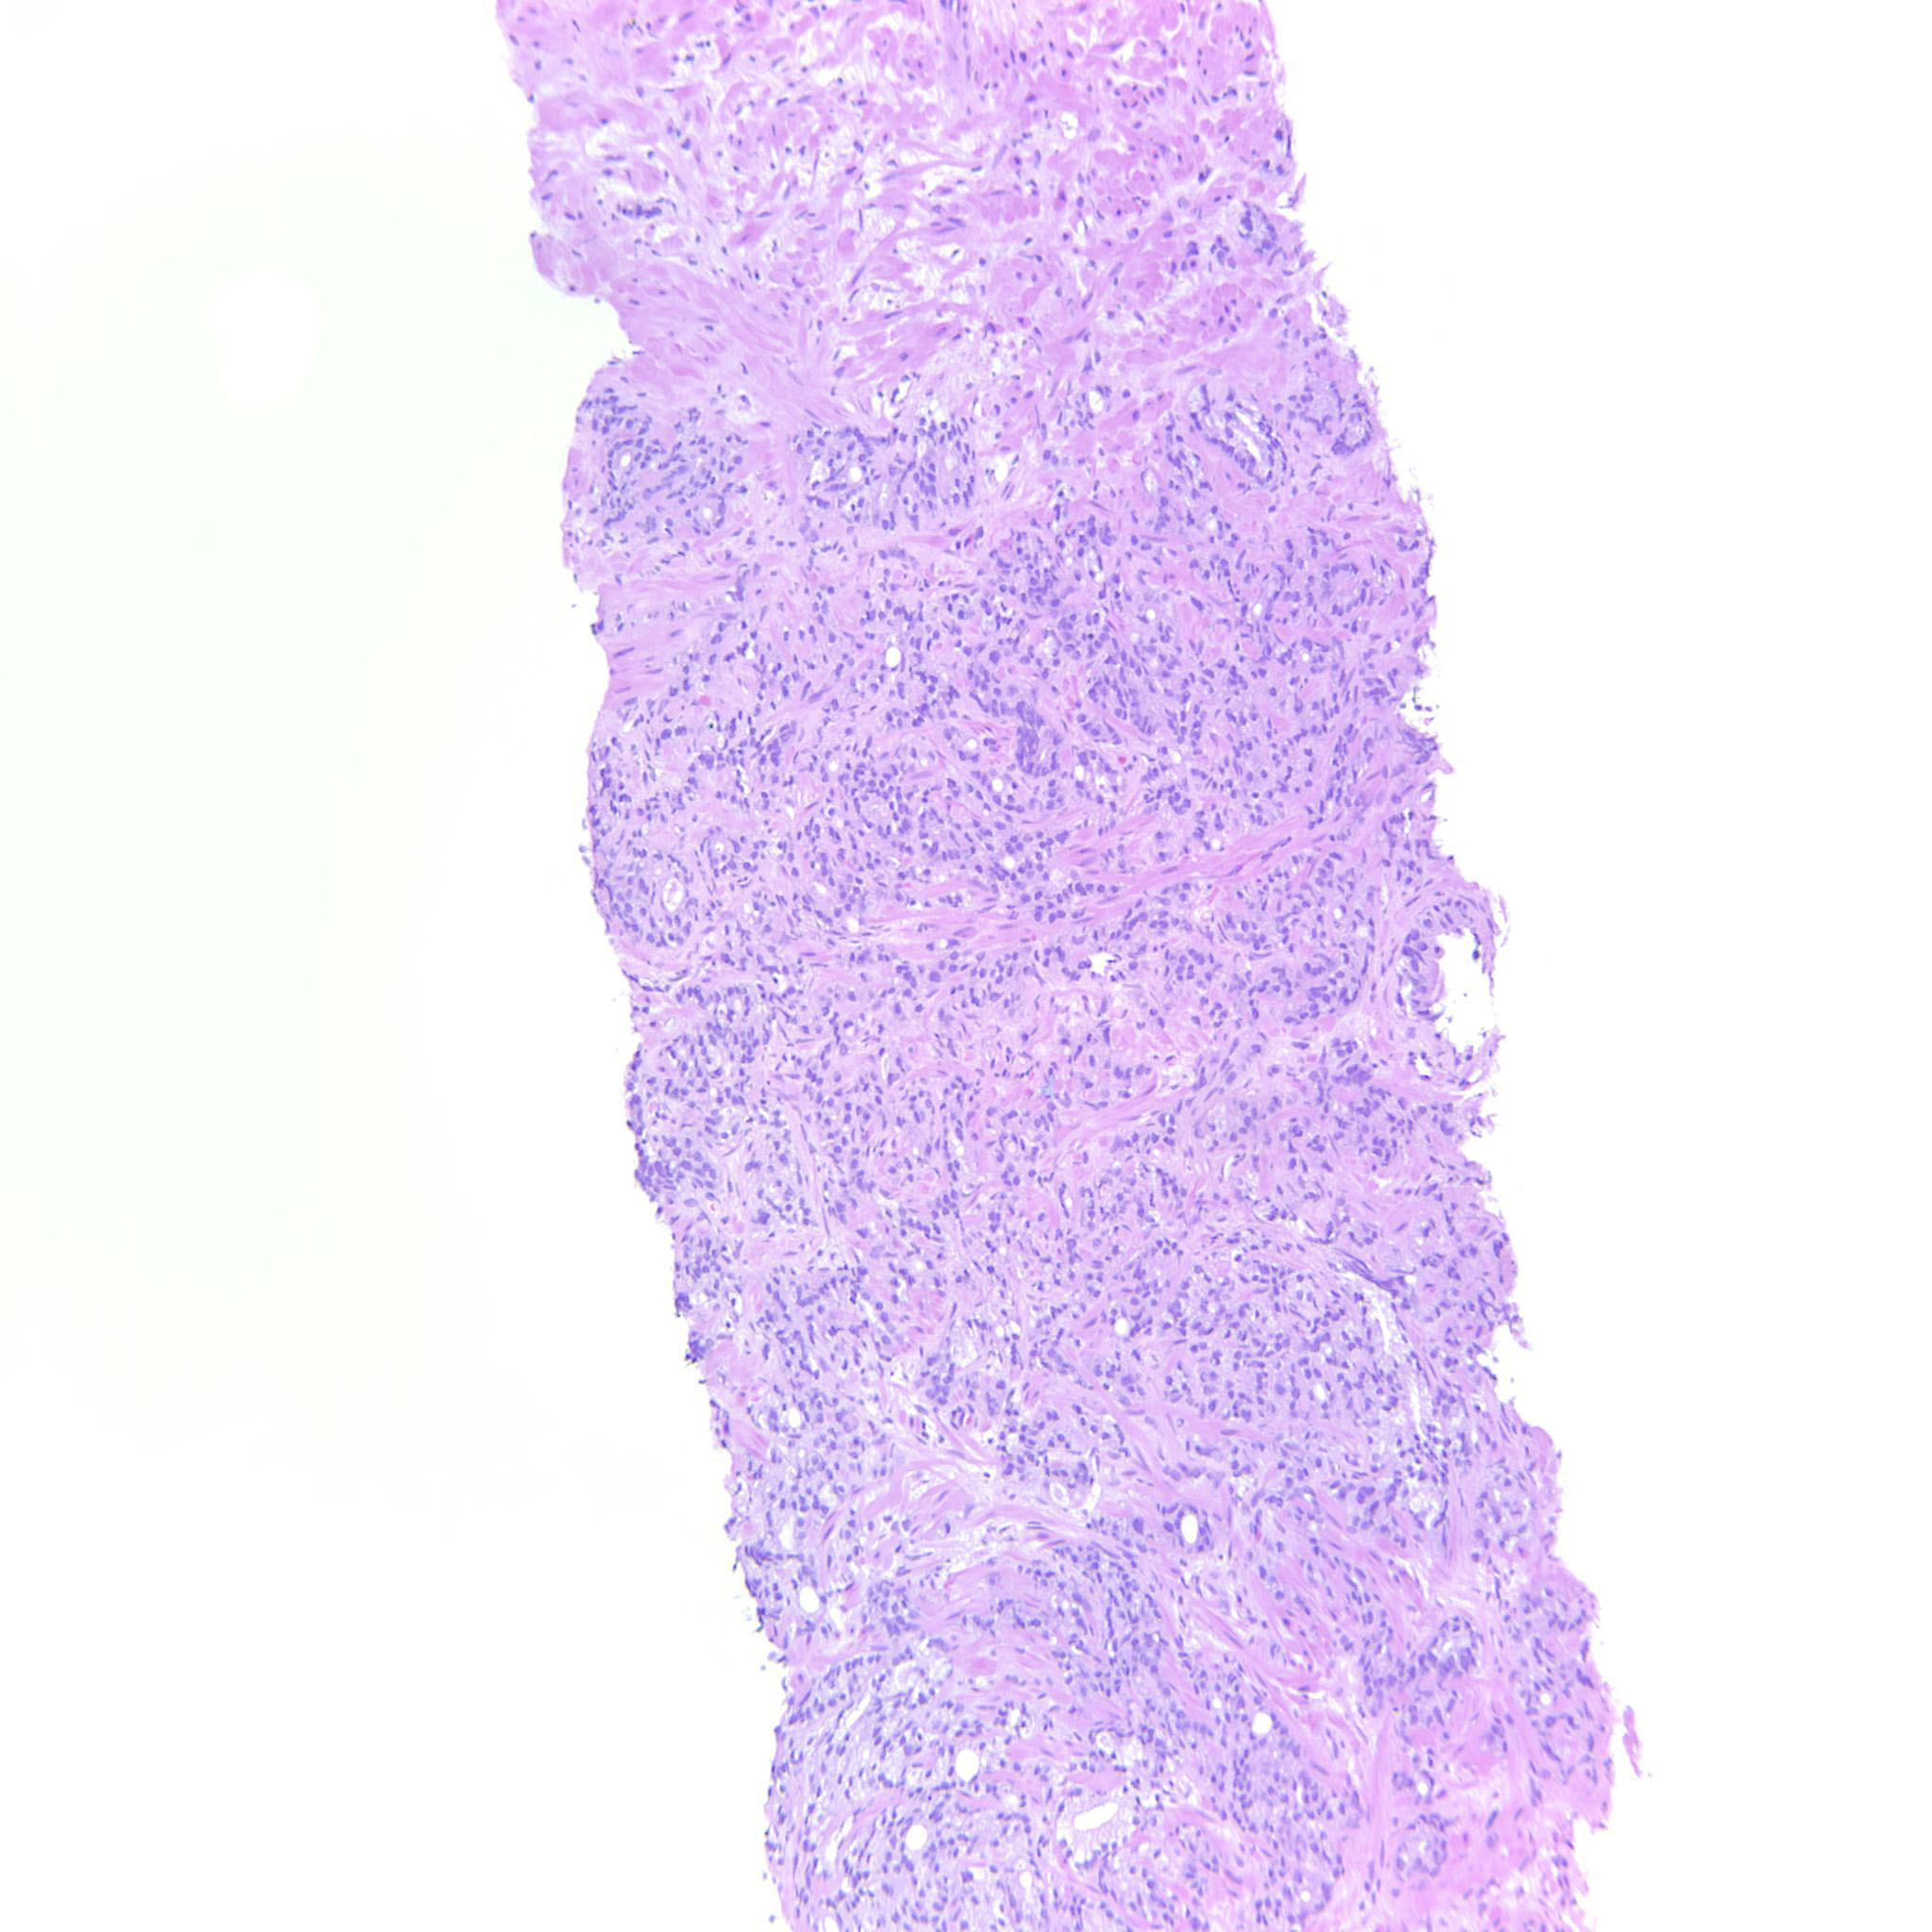

Consensus grade: GS 9-10 (ISUP 5)

Case description (by case creator):

4+5=9 where the GP5 component infiltrates diffusely in strands and single cells.